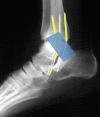

Ankle sonography is one of the most commonly ordered examinations in the field of osteoarticular imaging, and it requires intimate knowledge of the anatomic structures that make up the joint. For practical purposes, the examination can be divided into four compartments, which are analyzed in this pictorial essay: the anterior compartment, which includes the tibialis anterior, extensor hallucis longus, and extensor digitorum longus tendons; the accessory peroneus tertius tendon; and the extensor retinaculum; the medial compartment (tibialis posterior, flexor digitorum longus, and flexor hallucis longus tendons; the flexor retinaculum; the medial collateral-or deltoid-ligament, and the neurovascular bundle); the lateral compartment (peroneus longus, peroneus brevis, and peroneus quartus tendons; superior and inferior peroneal retinacula, lateral collateral ligament); and the posterior compartment (Achilles tendon, plantaris tendon, Kagar's triangle, superficial, and deep retrocalcaneal bursae). Scanning techniques are briefly described to ensure optimal visualization of the various anatomic structures.